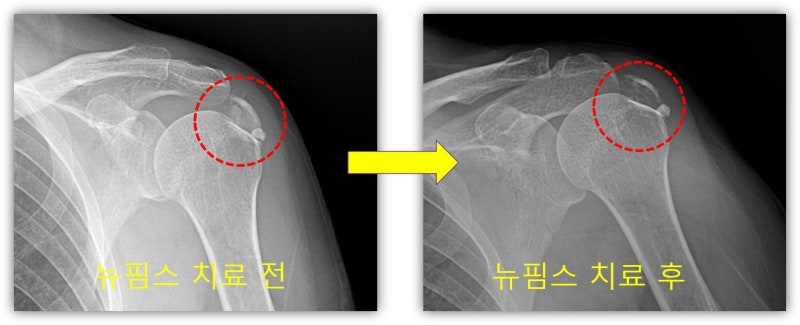

사진과 같이 석회분쇄흡입술을 시행하여 많은 양의 석회를 제거하였습니다.

뉴핌스 치료 후 사진과 같이 석회가 많이 제거된 x-ray 를 확인할 수 있습니다. 조금 석회가 남아 있으나 향 후 체외충격파 치료를 추가적으로 시행하면 완전히 제거가 될 것으로 사료됩니다. 환자는 시술 다음날 부터 통증이 거의 없고 팔도 잘 움적여 진다며 환하게 웃으십니다. 석회성 건염 치료는 그냥 통증만 제어한다고 해결되지 않습니다. 석회를 제거해야만 석회성 건염에서 탈출할 수 있습니다. 석회성 건염은 뉴핌스치료가 탁월한 효과를 보입니다. 이제 석회성 건염의 고통에서 수술 없이 완전히 벗어날 수 있습니다.